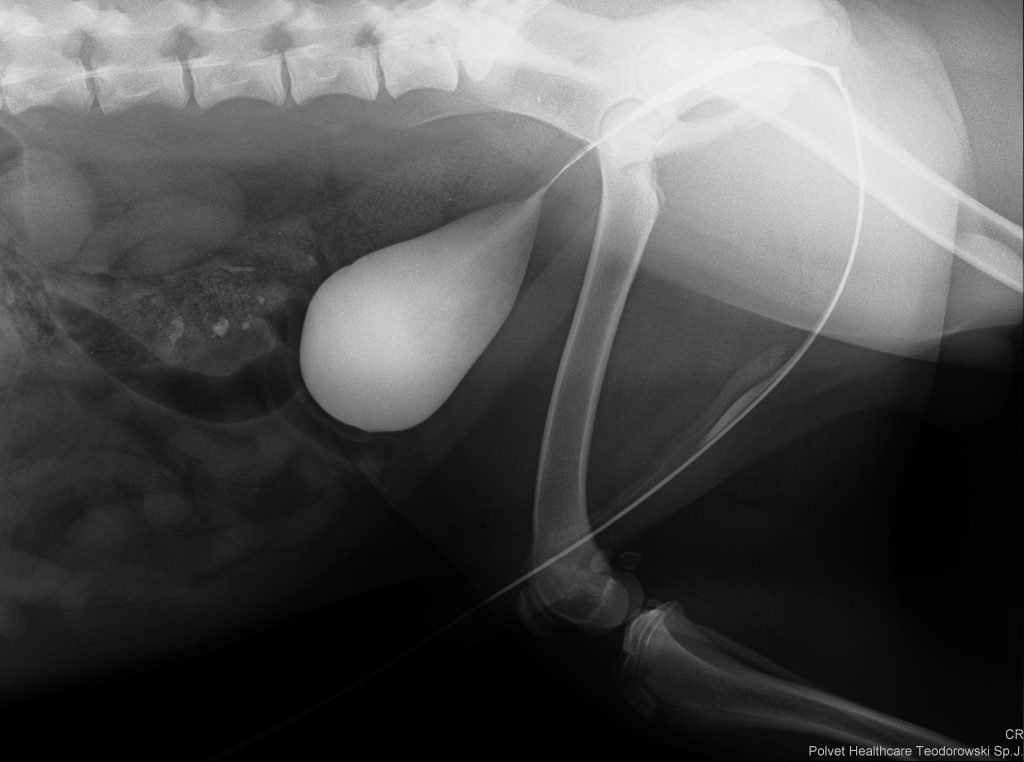

RTG jamy brzusznej

Pozwala wykryć niektóre typy kamieni moczowych.